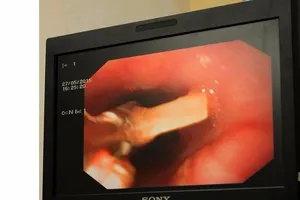

Xương cá hình cây dù chui vào phổi

Hóc xương cá tám tháng mà không biết